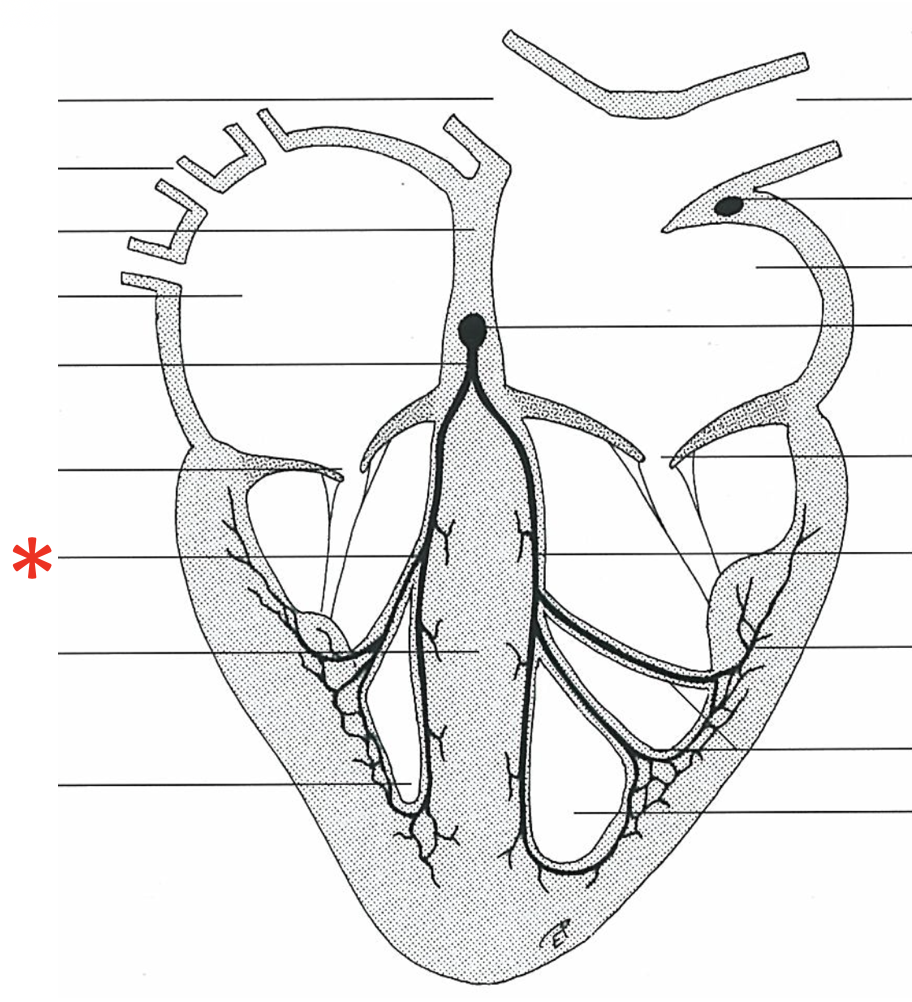

Paraconal Interventricular Branch

Septal Branch

Bundle of His

Left Crus

Right Crus

Purkinje Fibres

Left Ventricle

Sinoatrial Node

Right Atrium

Atrioventricular Node

Cranial Vena Cava